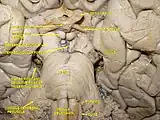

Pons in the brainstem | |

Anteroinferior view of the medulla oblongata and pons | |

The pons (pl.: pontes; from Latin pons, "bridge") is part of the brainstem that in humans and other mammals, lies inferior to the midbrain, superior to the medulla oblongata and anterior to the cerebellum.

The pons is also called the pons Varolii ("bridge of Varolius"), after the Italian anatomist and surgeon Costanzo Varolio (1543–75).[1] This region of the brainstem includes neural pathways and tracts that conduct signals from the brain down to the cerebellum and medulla, and tracts that carry the sensory signals up into the thalamus.[2]

Structure

The pons in humans measures about 2.5 centimetres (0.98 in) in length.[2] It is the part of the brainstem situated between the midbrain and the medulla oblongata,[3] and in front of the cerebellum. The horizontal medullopontine sulcus demarcates the boundary between the pons and medulla oblongata on the ventral aspect of the brainstem, and the roots of cranial nerves VI/VII/VIII emerge from the brainstem along this groove.[4] The junction of pons, medulla oblongata, and cerebellum forms an angle - the cerebellopontine angle.[5] The superior pontine sulcus separates the pons from the midbrain.[6] Posteriorly, the pons curves on either side into a middle cerebellar peduncle.[3]